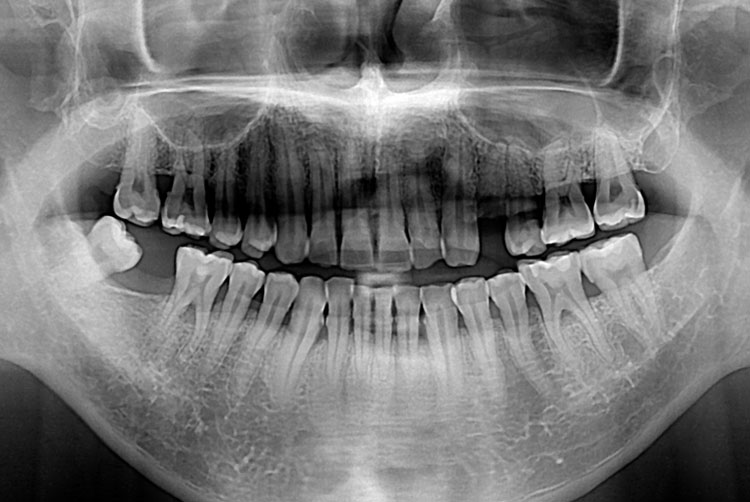

[임플란트] 임플란트

치료후 : 2018-06-15

세종치과는 많은 환자와 다양한 케이스를 바탕으로 항상 편안한 임플란트 수술을 제공하고자 노력하고,

오래동안 튼튼히 쓸 수 있는 임플란트 수술을 가장 큰 목표로 삼고 있습니다.